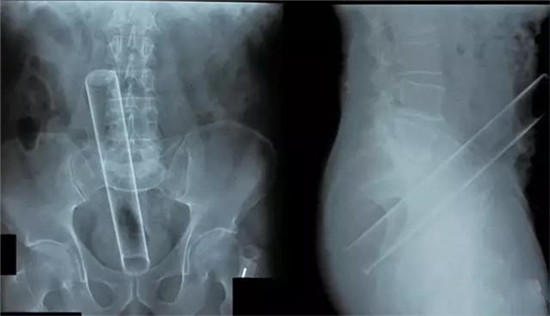

大肠里的擀面杖。男性

这是做饺子皮用的擀面杖。对,全部塞进去了。你知道怎么看男女吗?看骨盆的角度。

取出的方法如同上面。